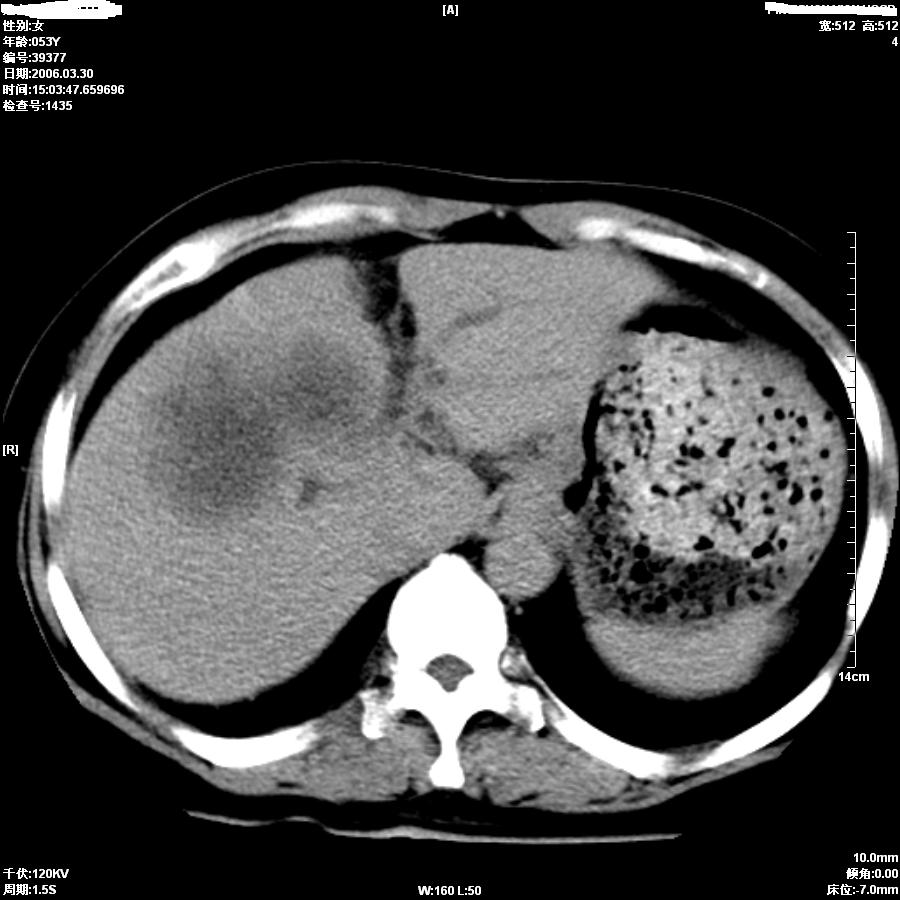

女,50岁,上腹部憋胀,疼痛月余。做增强刚打了50ml造影剂病人就出现了较重的过敏,所以强化不成功。

平扫第8图胆总管内似见结石,上部胆道扩张,肝内片影无强化,胆囊不清,胃小弯壁略厚。

考虑1胆结石伴低微弹道梗阻及肝内感染2胆管癌。

因为没有完整的强化,该病例我首先考虑是肝内胆管细胞癌.患者因为有过敏我建议行mri.

从平扫:肝脏肿块,胰头周围结构不清似有结节。考虑恶性肿瘤(首先要排外肝胆感染病变)。胆管癌>肝癌。建议mri。

如果胆囊未切除,首先考虑胆囊癌肝侵犯。

中老年妇女,肝门、胆囊区病变,病变实体形态欠清楚,胆囊癌可能性极大。

鉴别诊断:肝癌;胆管癌;

理由:1、低密度病灶,动脉期末有一点强化。

2、左肝内胆管扩张。

3、肝门区胆管壁静脉期有强化。